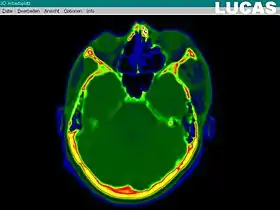

The most important component for CAS is the development of an accurate model of the patient. This can be conducted through a number of medical imaging technologies including CT, MRI, x-rays, ultrasound plus many more. For the generation of this model, the anatomical region to be operated has to be scanned and uploaded into the computer system. It is possible to employ a number of scanning methods, with the datasets combined through data fusion techniques. The final objective is the creation of a 3D dataset that reproduces the exact geometrical situation of the normal and pathological tissues and structures of that region. Of the available scanning methods, the CT is preferred,[1] because MRI data sets are known to have volumetric deformations that may lead to inaccuracies. An example data set can include the collection of data compiled with 180 CT slices, that are 1 mm apart, each having 512 by 512 pixels. The contrasts of the 3D dataset (with its tens of millions of pixels) provide the detail of soft vs hard tissue structures, and thus allow a computer to differentiate, and visually separate for a human, the different tissues and structures. The image data taken from a patient will often include intentional landmark features, in order to be able to later realign the virtual dataset against the actual patient during surgery. See patient registration.

Image analysis and processing

Image analysis involves the manipulation of the patients 3D model to extract relevant information from the data. Using the differing contrast levels of the different tissues within the imagery, as examples, a model can be changed to show just hard structures such as bone, or view the flow of arteries and veins through the brain.